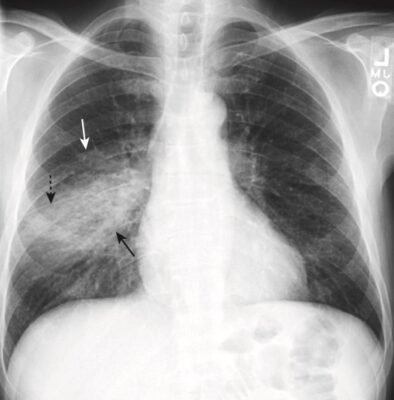

- Bệnh vùng khoang chứa khí có thể có hình ảnh phế quản chứa khí /(khí phế quản đồ)(air bronchogram).

- Khả năng nhìn thấy không khí trong phế quản vì bệnh lý khoang chứa khí xung quanh được gọi là hình ảnh phế quản chứa khí

- Hình ảnh phế quản chứa khí là một dấu hiệu của bệnh lý khoang chứa khí.

- Bình thường không nhìn thấy được phế quản vì thành của chúng rất mỏng, chứa không khí và được bao quanh bởi không khí. Khi một thứ gì đó như chất dịch hoặc mô mềm thay thế không khí bình thường bao quanh phế quản, thì không khí bên trong phế quản trở nên có thể nhìn thấy dưới dạng một loạt cấu trúc hình ống phân nhánh, màu đen – đây là hình ảnh phế quản chứa khí (Hình 3).